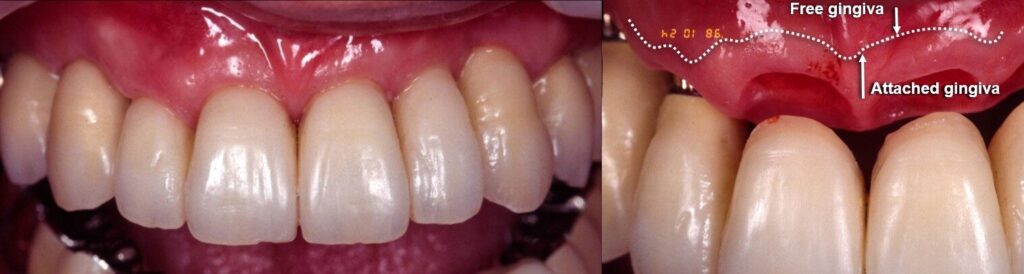

臨床例